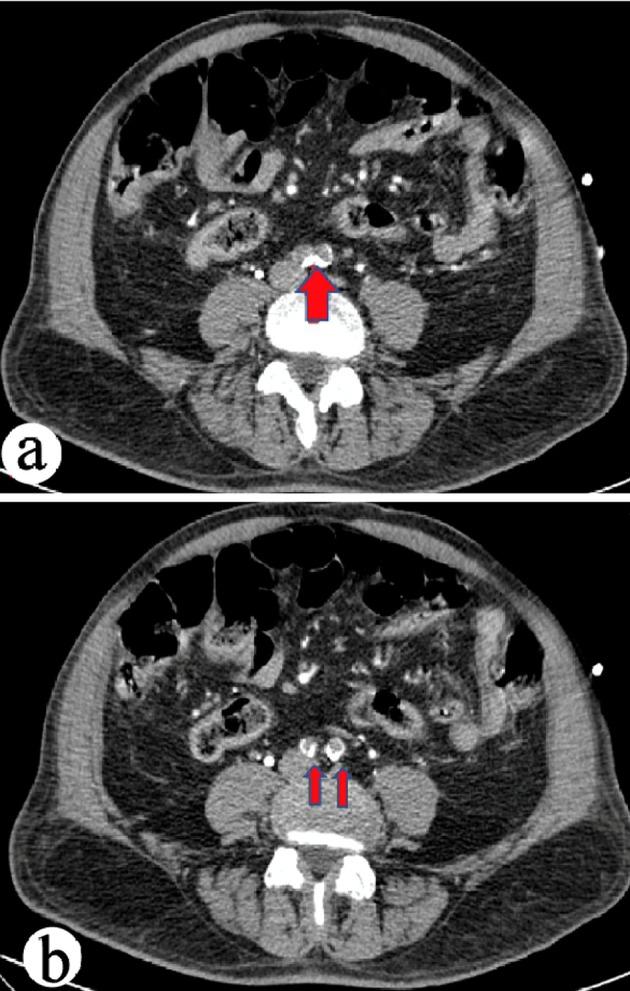

Left ventricular thrombus (LVT) is a well-known complication of myocardial infarction (MI) leading to significant morbidity and mortality. LVT can also lead to systemic thromboembolic events causing threatening limb ischemia. We report a rare case of critical bilateral limb ischemia that resulted from peripheral embolization of LVT post MI, which was managed successfully by emergent surgical intervention and anticoagulation. A 74-year-old male with a medical history of hypertension, diabetes, hyperlipidemia and coronary artery disease status post stenting of the left anterior descending and left circumflex arteries presented to the emergency department with typical chest pain and progressive shortness of breath. Cardiac troponin levels on admission were 35 ng/mL of blood. The patient subsequently underwent emergent cardiac catheterization which revealed significant triple vessel disease, and was referred for coronary artery bypass grafting (CABG) surgery. Transthoracic and transesophageal echocardiograms revealed the presence of an apical aneurysm with chronic organized mobile thrombus at the apex. Post CABG, the patient complained of excruciating right leg pain. Computed tomography (CT) angiogram of the abdominal aorta and lower extremities revealed a large embolus at the aortic bifurcation occluding the right and nearly occluding the left common iliac arteries and thrombus in the right popliteal artery. He underwent emergent vascular surgery with resolution of his symptoms and remained without further complications. The incidence of LVT remains high in post-MI patients, and complications of LVT are known to include thromboembolic events. Peripheral embolization of acute or chronic LVT leading to bilateral distal embolization and critical limb ischemia remains a rare occurrence. This case report aims to aid clinicians to recognize and promptly manage LVT and related arterial thromboembolic events with anticoagulation and emergent surgical intervention if limb ischemia develops.

左心室血栓(LVT)是心肌梗死(MI)的一种众所周知的并发症,可导致严重的发病率和死亡率。LVT还可导致全身血栓栓塞事件,引起威胁肢体的缺血。我们报告一例罕见的严重双侧肢体缺血病例,该病例由心肌梗死后LVT的外周栓塞引起,通过紧急手术干预和抗凝治疗成功处理。一名74岁男性,有高血压、糖尿病、高脂血症病史,左前降支和左旋支动脉支架置入术后冠心病,因典型胸痛和进行性气短就诊于急诊科。入院时心肌肌钙蛋白水平为每毫升血液35纳克。患者随后接受了紧急心脏导管检查,显示存在严重的三支血管病变,并被转诊进行冠状动脉旁路移植术(CABG)。经胸和经食管超声心动图显示心尖部有一个室壁瘤,心尖部有慢性机化的活动血栓。CABG术后,患者抱怨右腿剧痛。腹主动脉和下肢的计算机断层扫描(CT)血管造影显示主动脉分叉处有一个大栓子,阻塞了右侧并几乎阻塞了左侧髂总动脉,右侧腘动脉有血栓。他接受了紧急血管手术,症状得到缓解,且未再出现进一步并发症。心肌梗死后患者中LVT的发生率仍然很高,已知LVT的并发症包括血栓栓塞事件。急性或慢性LVT的外周栓塞导致双侧远端栓塞和严重肢体缺血仍然很少见。本病例报告旨在帮助临床医生认识并及时处理LVT以及相关的动脉血栓栓塞事件,若发生肢体缺血则采用抗凝和紧急手术干预。